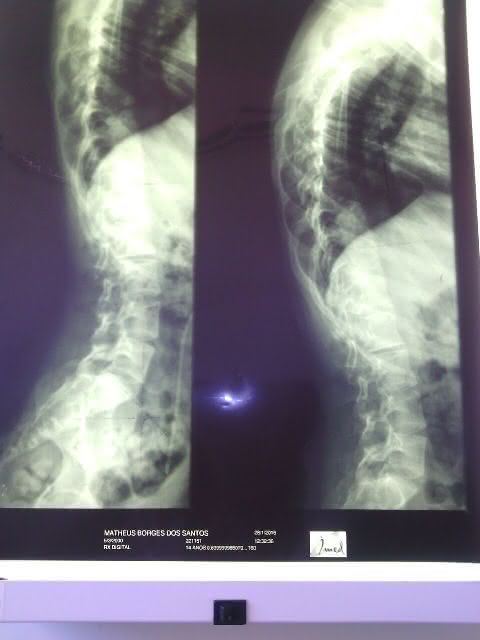

A equipe do portal visitou a residência do vigilante e da professoram que dedicam suas vidas ao pequeno Mateus Domingos dos Santos de 15 anos, que sofre de escoliose que é o encurvamento anormal da coluna vertebral, que provoca dor lombar e nas costas e pode morre caso não consiga realizar uma cirurgia nos próximos meses.

Durante duas horas, os pais contaram ao radialista João Miguel toda história de dor e sofrimento, que aumentou no decorrer dos dias com a notícia, que a escoliose vem atrofiando alguns órgãos que pode levar a morte do seu filho.

- Raio -X da coluna